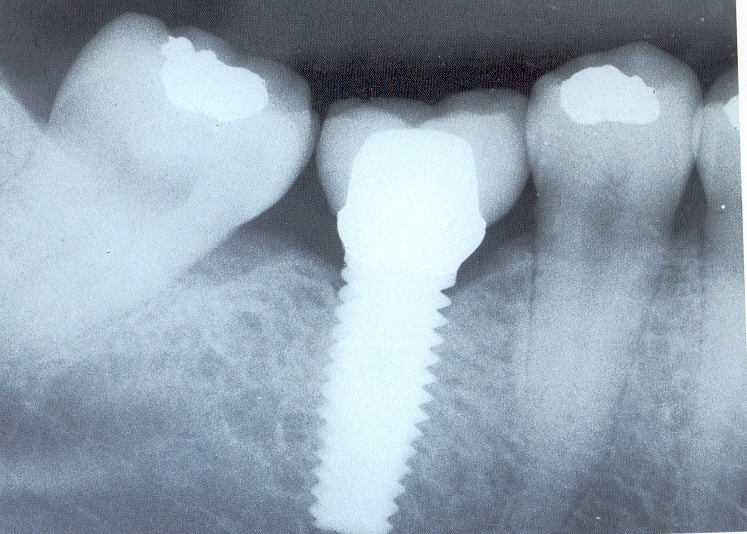

Son estructuras de titanio de formas similares a las raíces de los dientes naturales, que son colocadas en los huesos de los maxilares. Una vez que los implantes se han integrado al organismo mediante un proceso natural por el cuál el titanio y el hueso se unen, y es llamado “óseointegración”. Posteriormente a estas estructuras se les atornilla la parte del diente o dientes que se substituyen, remplazando naturalmente al diente en función y estética. Este procedimiento en el mayor de los casos es realizado SIN dolor.